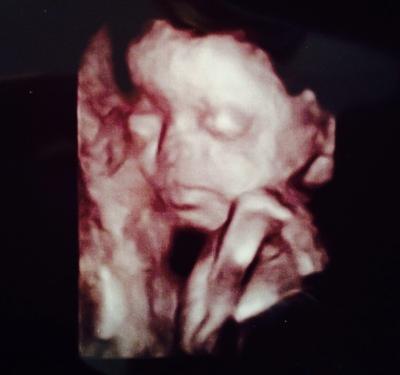

Hey, war heute wieder beim FA: Zuckertest überstanden, alles in Ordnung. Allerdings sind meine Leukos so erhöht, dass ich einmalig ein Antibiotikum nehmen soll. Die Kleine lag bisher jedes Mal in BEL. Ich hoffe sehr, dass sich das gegen Ende der Schwangerschaft noch ändern wird. Wie liegen denn eure Babies? LG, JCB

Bild zu Kindslage? - Forum für Mai - Mamis